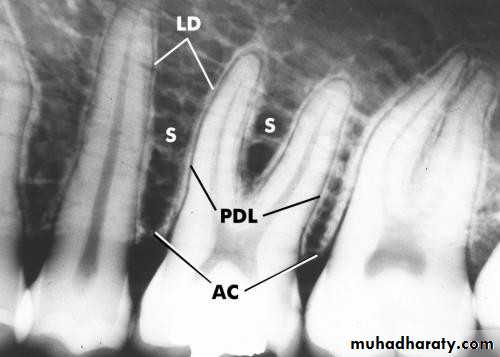

• Radiographic indicators of occlusal trauma :

• Widened PDL.

• Bone loss.• Root resorption.

• Periodontal Examination Radiographic Assessment

• Periodontal Examination• Radiographic Assessment

• Bone Loss• Horizontal Vertical

• Endodontic involvement Root deposits